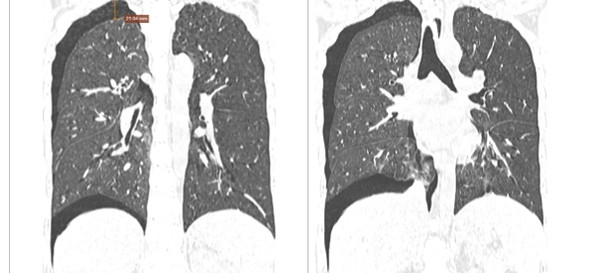

Tại thời điểm khám, BN có mệt, khó thở, hụt hơi nhất là khi gắng sức, ho nhiều và có đờm trắng; thăm khám thấy thông khí giảm. Sau thăm khám đầu vào, bệnh nhân được chụp CT phổi và làm các xét nghiệm đánh giá tình trạng tim mạch, tiểu đường cũng như toàn trạng của cơ thể.

Kết quả CT phổi có hình ảnh tổn thương kính mờ, dày tổ chức kẽ và dải xơ dưới màng phổi hai bên, hướng đến tổn thương hậu Covid-19. Đo chức năng hô hấp thấy giảm lưu lượng các nhánh phế quản vừa và nhỏ.